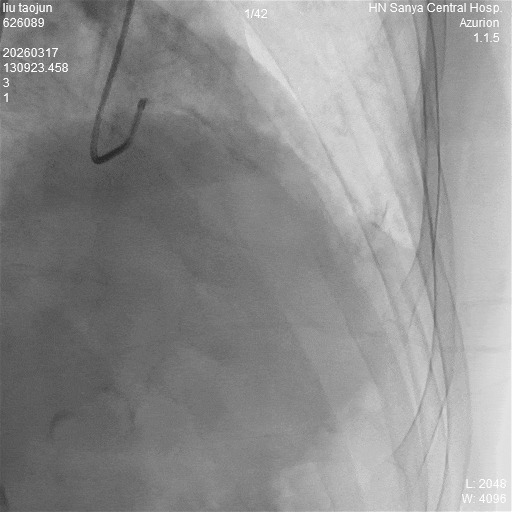

▲ 术前